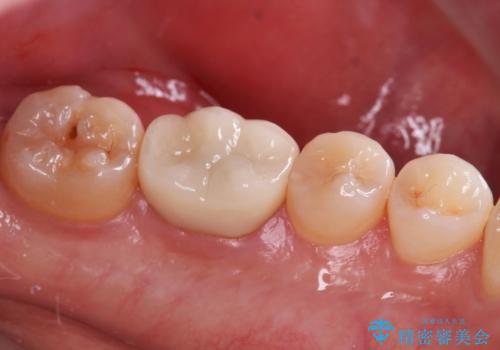

銀歯の下の虫歯|オールセラミッククラウン

担当医 河野豊嘉

奥歯に虫歯があると言われた セラミッククラウンでキレイで長持ちする歯へ

担当医 榊原康平